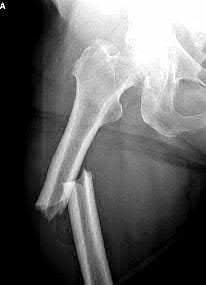

A 35-year-old-male sustains the fracture seen in Figure A. Which of the following reduction forces must be applied to the proximal fragment to correct the deformity commonly seen in these fractures?

Figure A demonstrates a displaced subtrochanteric femur fracture with an intact lesser trochanter. The pull of iliopsoas on the lesser trochanter as well as the intact external rotators and gluteal musculature results in the the proximal fragment being in a flexed and externally rotated or abducted position (the most common post operative deformity). Reduction manuevers must be biologically friendly but also counteract the flexion/abduction moment. Lundy's review article discusses evaluation and treatment of subtrochanteric fractures. The review article details the various implants often used which include 95 degrees plates, femoral reconstruction nails, or trochanteric femoral nails with interlocking options. Lundy's article discourages the use of the 135 degree screw and side plate combo due to high failure rates in these fracture patterns. Bedi et al also review treatment of these fractures and discuss common

problems of malunion, nonunion, and implant failure. The article reviews reduction techniques that are soft tissue friendly, as well as the use of appropriate implants in these fracture types.